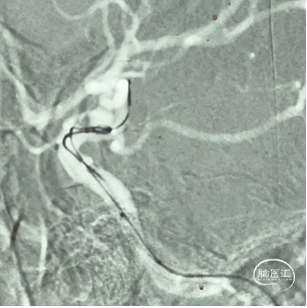

【XT-17超选入动脉瘤腔内】

【Perfiller®4mm*8cm-3D半推入】

利用微导丝引导XT-27支架微导管置于大脑中动脉远端,然后将泰杰伟业TJED-D-5.0-14 Nuva®血流导向密网支架(预期血管直径和长度4.5mm*19mm)沿着支架微导管顺利输送到位。

缓慢回撤微导管,在颈内动脉末端处,影像下观察支架头端轻松打开,确认支架远端锚定区域,完成远端定位后,采用推拉结合方式缓慢稳定释放Nuva®支架至完全覆盖动脉瘤瘤颈口,并确保支架贴合打开情况良好。

经栓塞微导管完全填入泰杰Perfiller®4mm*8cm-3D,再依次填入泰杰Perfiller®3mm*6cm-3D、Perfiller®2mm*4cm-3D、2枚Perfiller®1mm*2cm-3D。